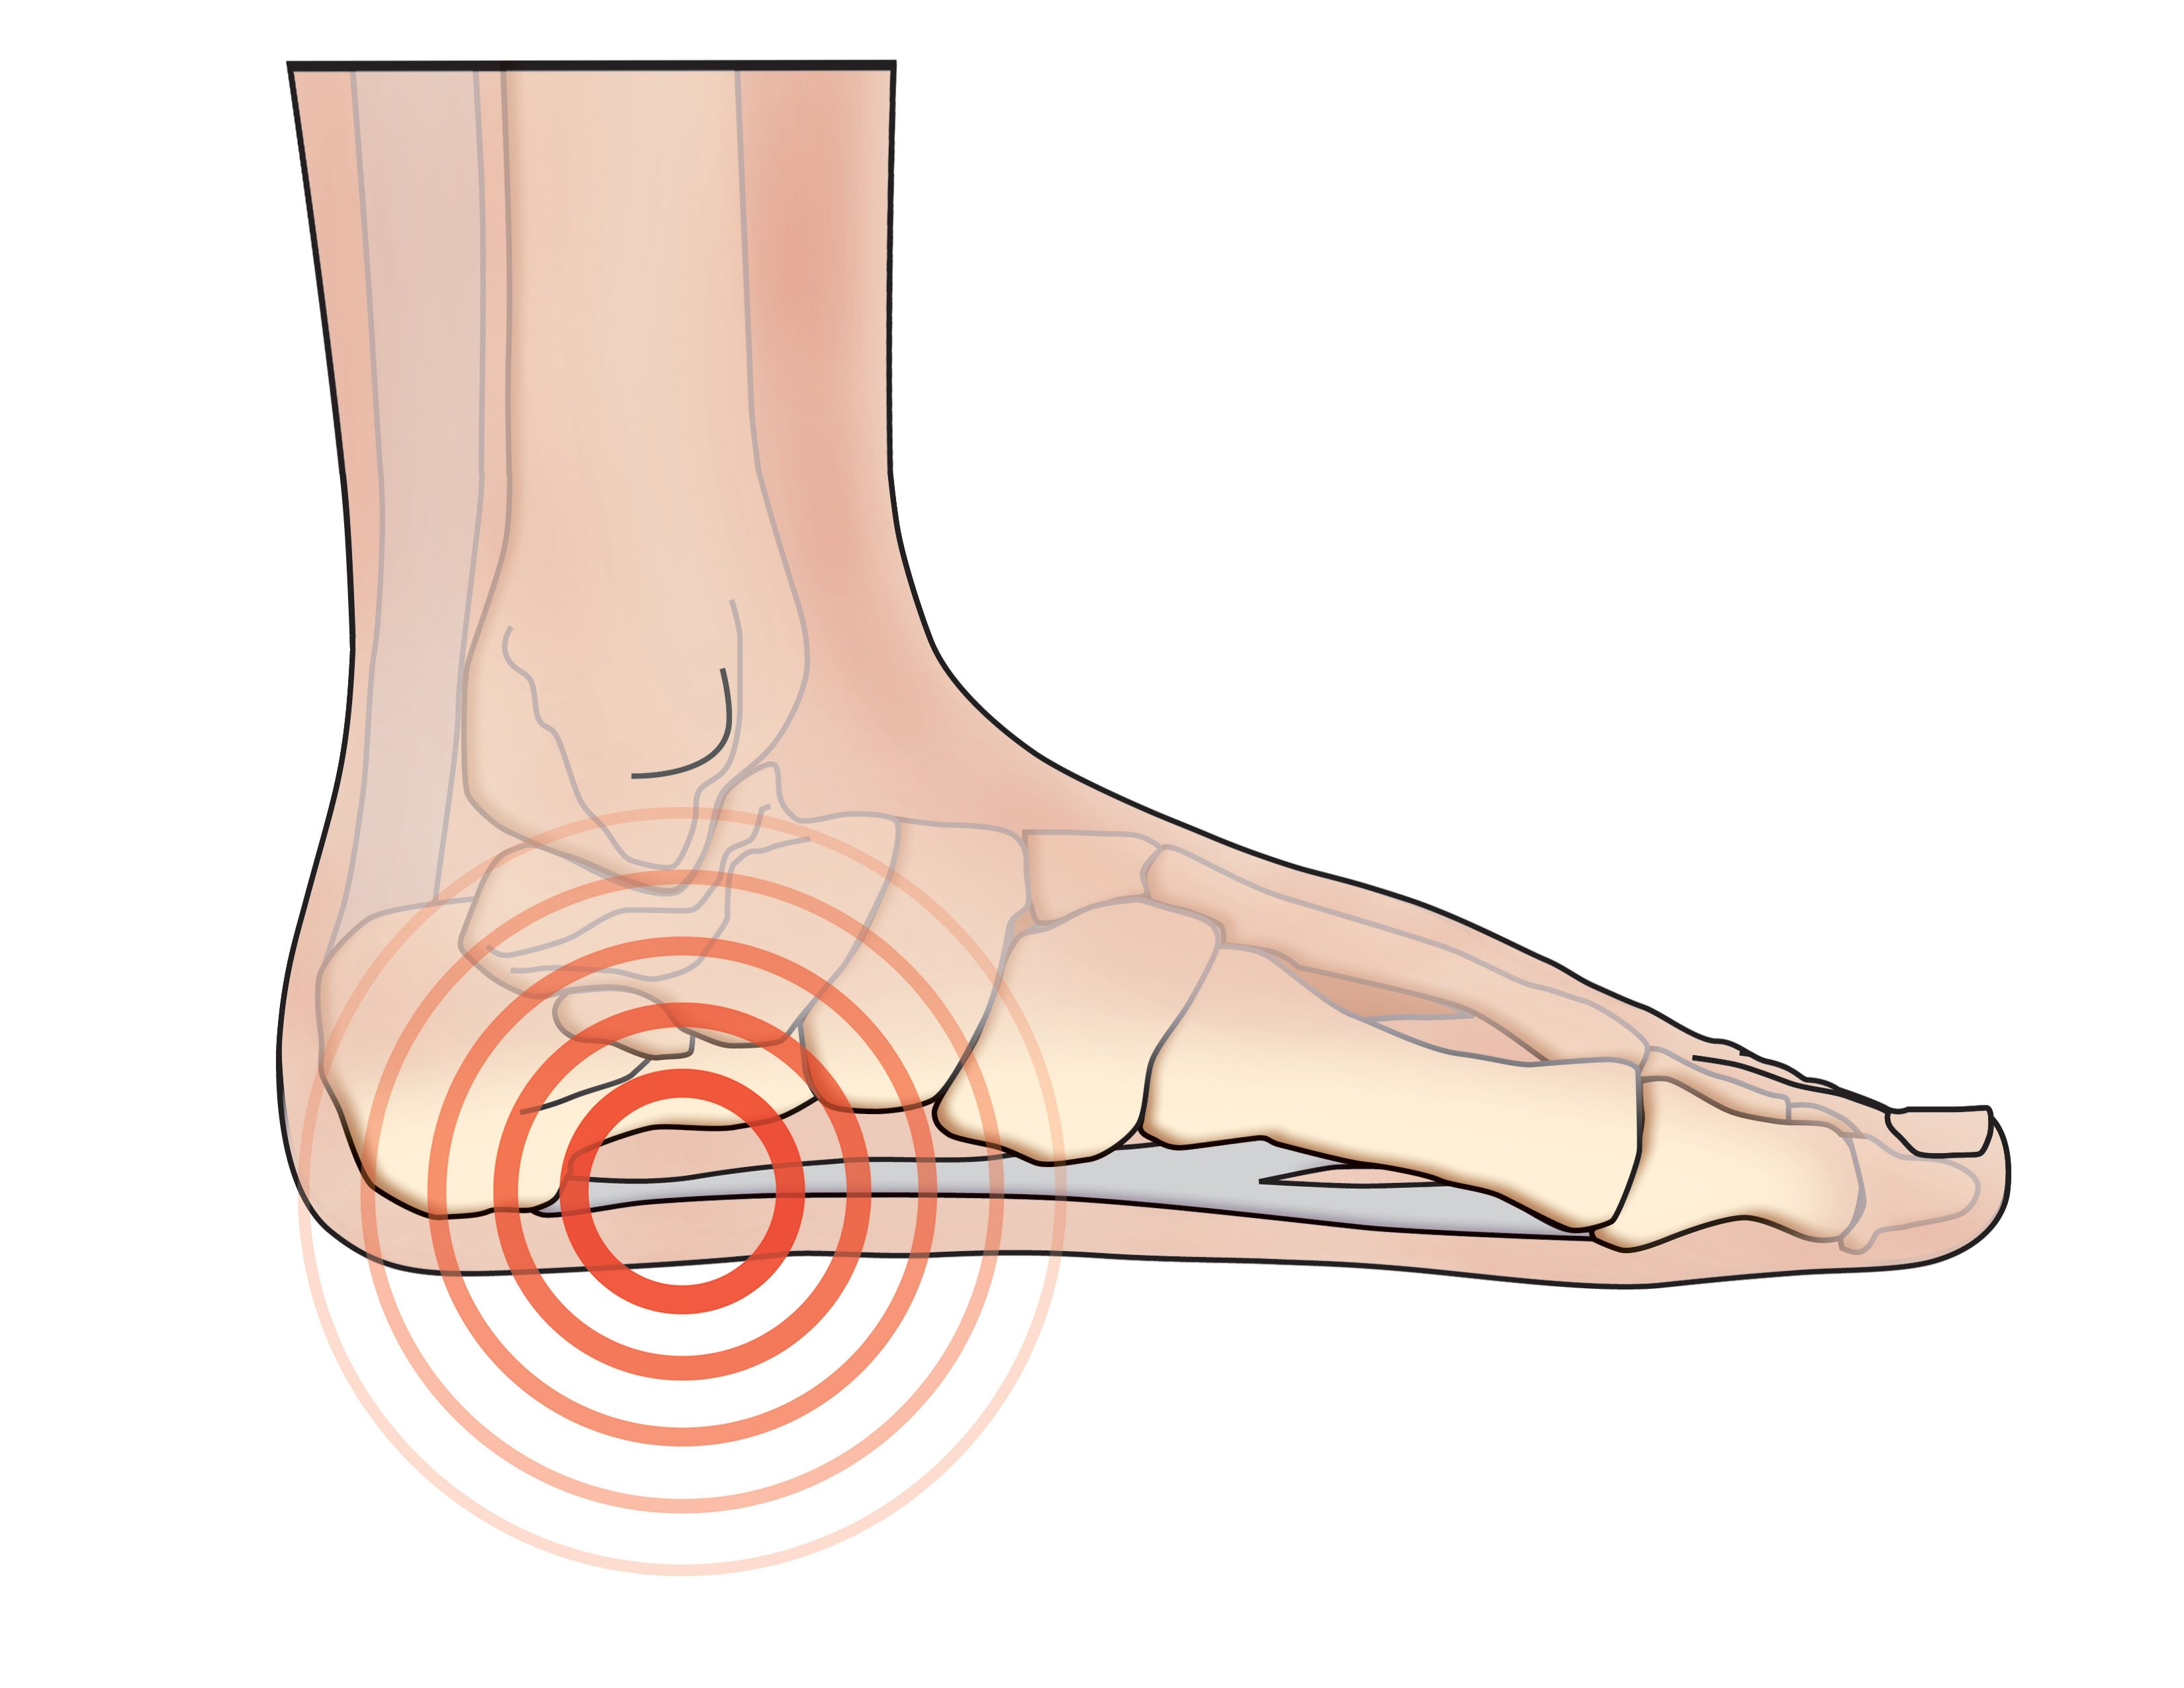

Mid Foot Pain Causes Symptoms Best Home Treatment

Flat Feet Pain Treatment Hyperhealth

Flat Feet Causes Symptoms Treatment Brisbane Physiotherapy